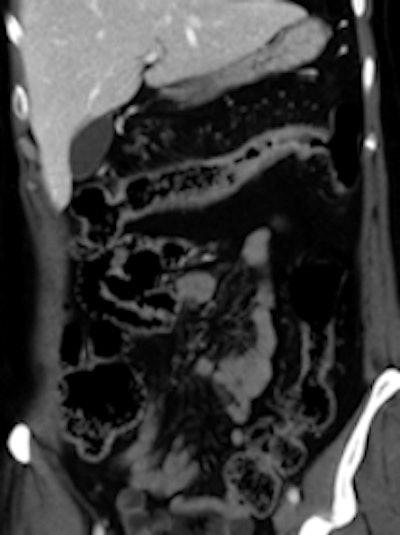

Left: Elderly patient presenting with low-grade bowel obstruction. Optical colonoscopy was denied due to patient's condition, and a CT with water enema was performed in order to detect a large lesion. This was the case because the patient had an almost occlusive cancer of the sigmoid. Right: Crohn's disease involving the transverse colon, with wall thickening and hyperhemia of the colonic vessels. All images courtesy of Dr. Yves Menu.The modalities appear to be becoming increasingly complementary. Follow-up programs can also include VC in association with OC. In patients requiring prolonged follow-up, both methods can be interleaved for the detection of polyps or recurrence.